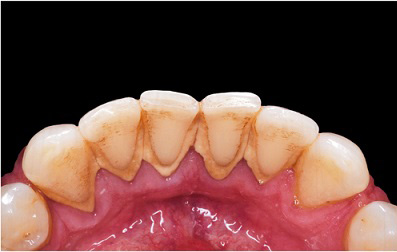

Periodontal diseases can be accelerated by a number of different factors. However, it is mainly caused by the bacteria found in dental plaque, a sticky colorless film that constantly forms on your teeth. If not carefully removed by daily brushing and flossing, plaque hardens into a rough, porous substance known as calculus (or tartar).

Bacteria found in plaque produces toxins or poisons that irritate the gums, which may cause them to turn red, swell and bleed easily. If this irritation is prolonged, the gums separate from the teeth, causing pockets (spaces) to form. As periodontal diseases progress, the supporting gum tissue and bone that holds teeth in place deteriorate. If left untreated, this leads to tooth loss.

The initial stage of treatment for periodontal disease is usually a thorough cleaning that may include scaling or root planing. The objective of these non-surgical procedures is to remove etiologic agents such as dental plaque and tartar, or calculus, which cause gingival inflammation and disease. Scaling and root planing can be used as a stand-alone treatment, or a preventative measure. They are commonly performed on cases of gingivitis and moderate to severe periodontal disease.

When scaling is performed, calculus and plaque that attaches to the tooth surfaces is removed. The process especially targets the area below the gum line, along the root. Scaling is performed with a special dental tool called an ultrasonic scaling tool. The scaling tool usually includes an irrigation process that can be used to deliver an antimicrobial agent below the gums to help reduce oral bacteria.